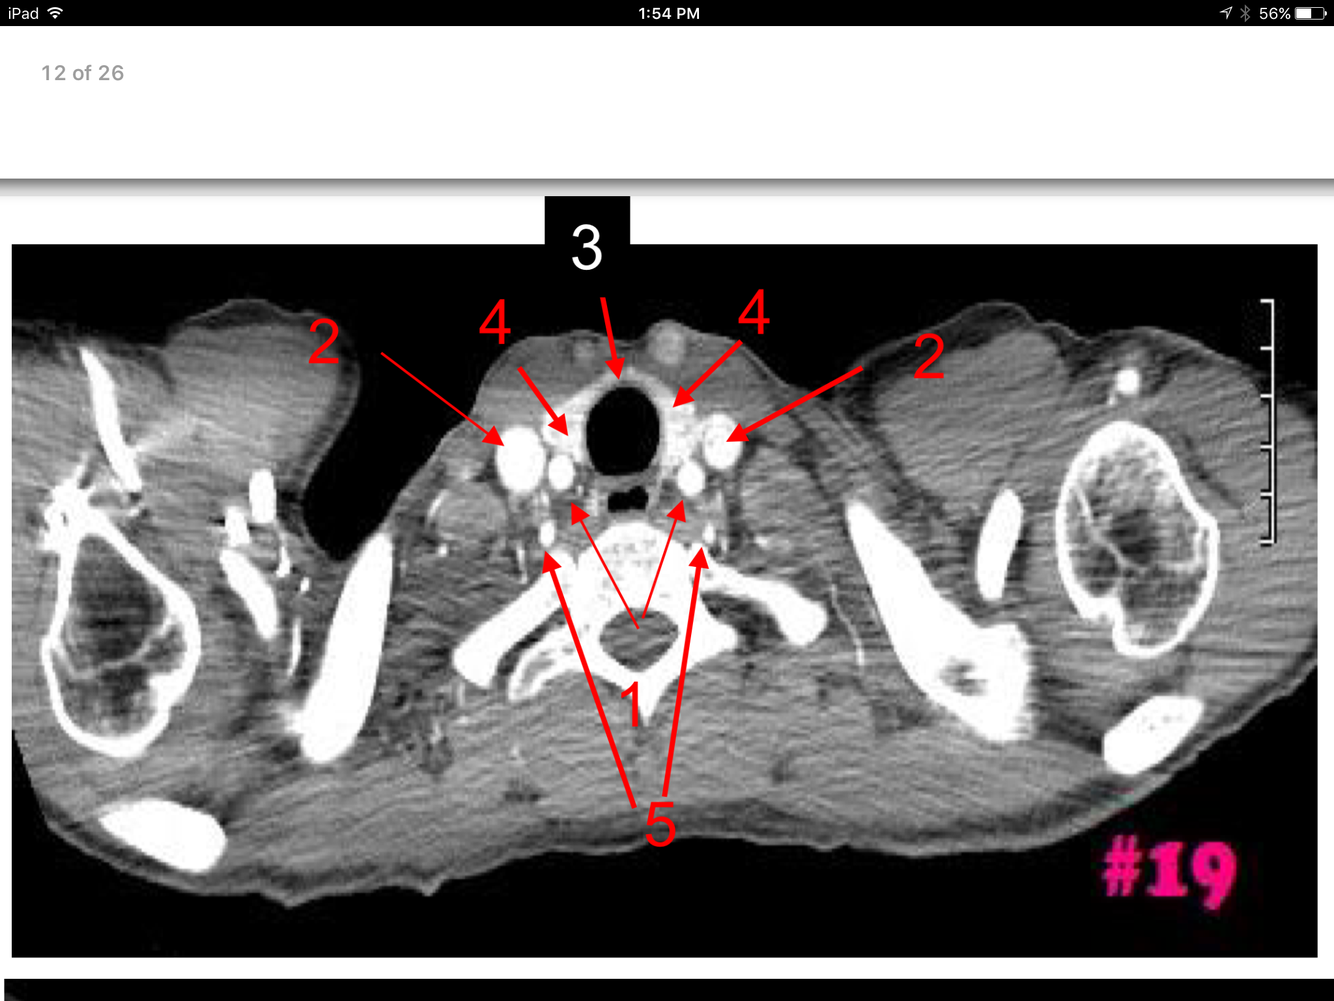

11

Rt and Lt common carotid arteries

Rt and Lt internal jugular veins

Rt and Lt lobes of the thyroid gland

Rt and Lt vertebral arteries